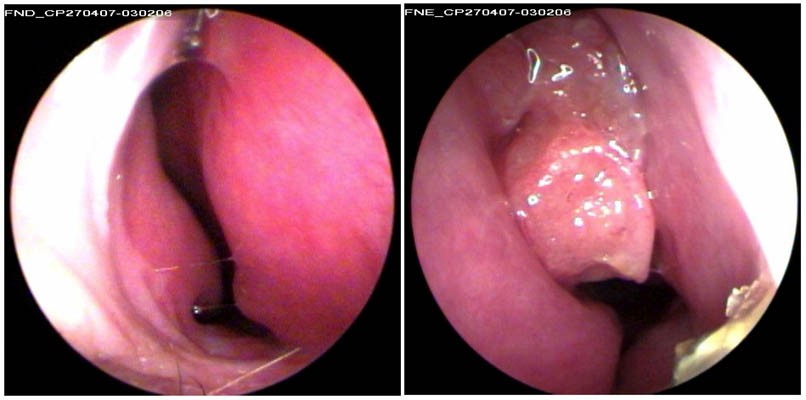

JFC Poliposis nasal bilateral.

JFC Rinosinusitis poliposa exteriorizándose por fosa nasal izquierda.

JFC Poliposis nasal